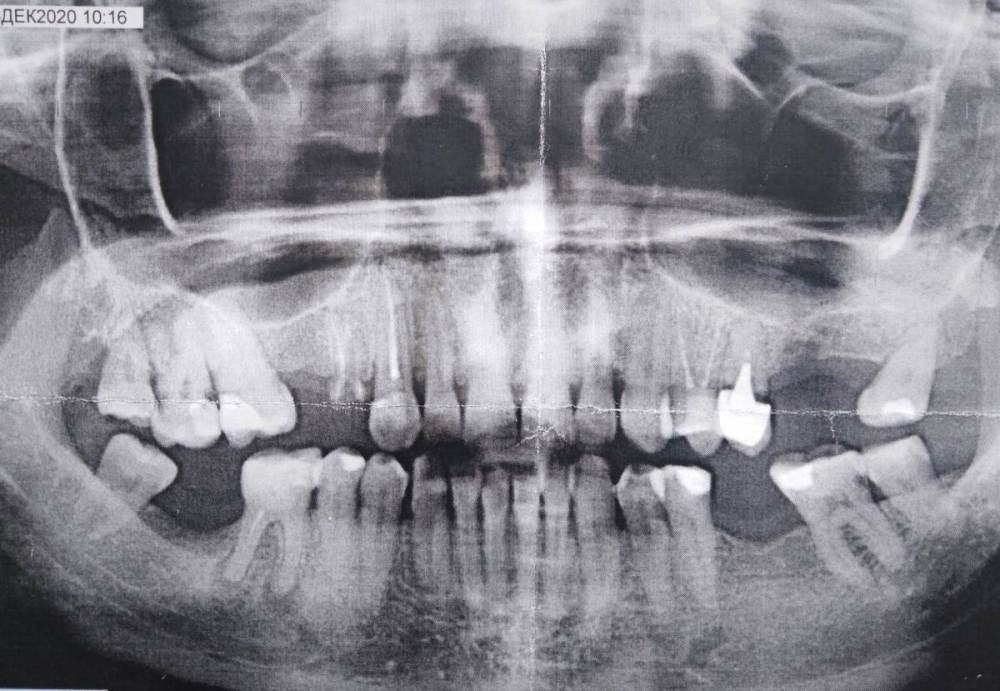

Хочу привести все зубы в порядок. Съёмные протезы не рассматриваю. Какой план действий? Что удалить и пполечить? В частности:надо ли удалять верхнюю 4 справа (вернее то, что от неё осталось). Можно ли ставить сразу все импланты? Какие лучше? Заранее спасибо за ответ.

1.8 1.4 2.8 3.8 4.8 и возможно 2.5

1.7 3.7 4.6